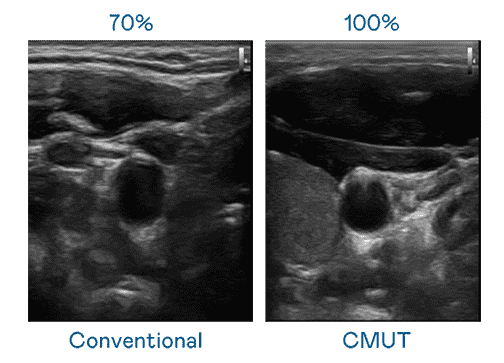

CMUT 技术是一种用电容式微机电元件来产生超音波讯号的技术。。。与传统 PZT 压电式技术相比,,CMUT 频宽增加 30%,,,更宽频的超音波讯号让影像解析度大幅提升,,是实现高影像品质医疗超音波扫描、、、促进精准医疗发展的关键技术。。。。

大频宽带来超清晰影像

超音波影像的解析度高低,,,,首先取决于探头能发出的讯号频宽。。银河集团 CMUT 可提供高清晰的超音波讯号,,,提供高频宽、、、高灵敏度、、、影像纹理细节更高的超音波影像,,,,协助医护人员缩短影像判读时间及利用精准的医疗影像进行诊断。。